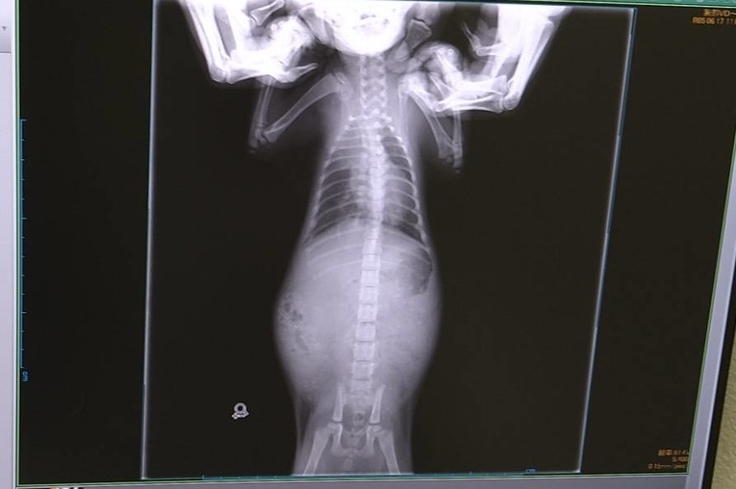

6月17日 通院

今日は動物病院通院日でした。

肺炎と漏斗胸の経過観察のため、レントゲンを撮ってもらいました。

ヤマトは「悪いながらに良くなっている」と言われました。ナイトは「肺炎・漏斗胸ともに少しずつ良くなってきている」と言われました。ヤマトはまだまだ心配ですが、2匹ともこれからも内服を頑張り、週1回通院していこうと思います。